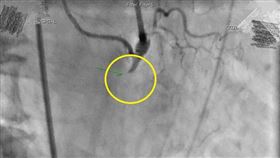

30年每天1.5包菸 心肌梗塞險死

名間鄉鳳梨進入產季,一名年約65歲的陳先生上禮拜採收...